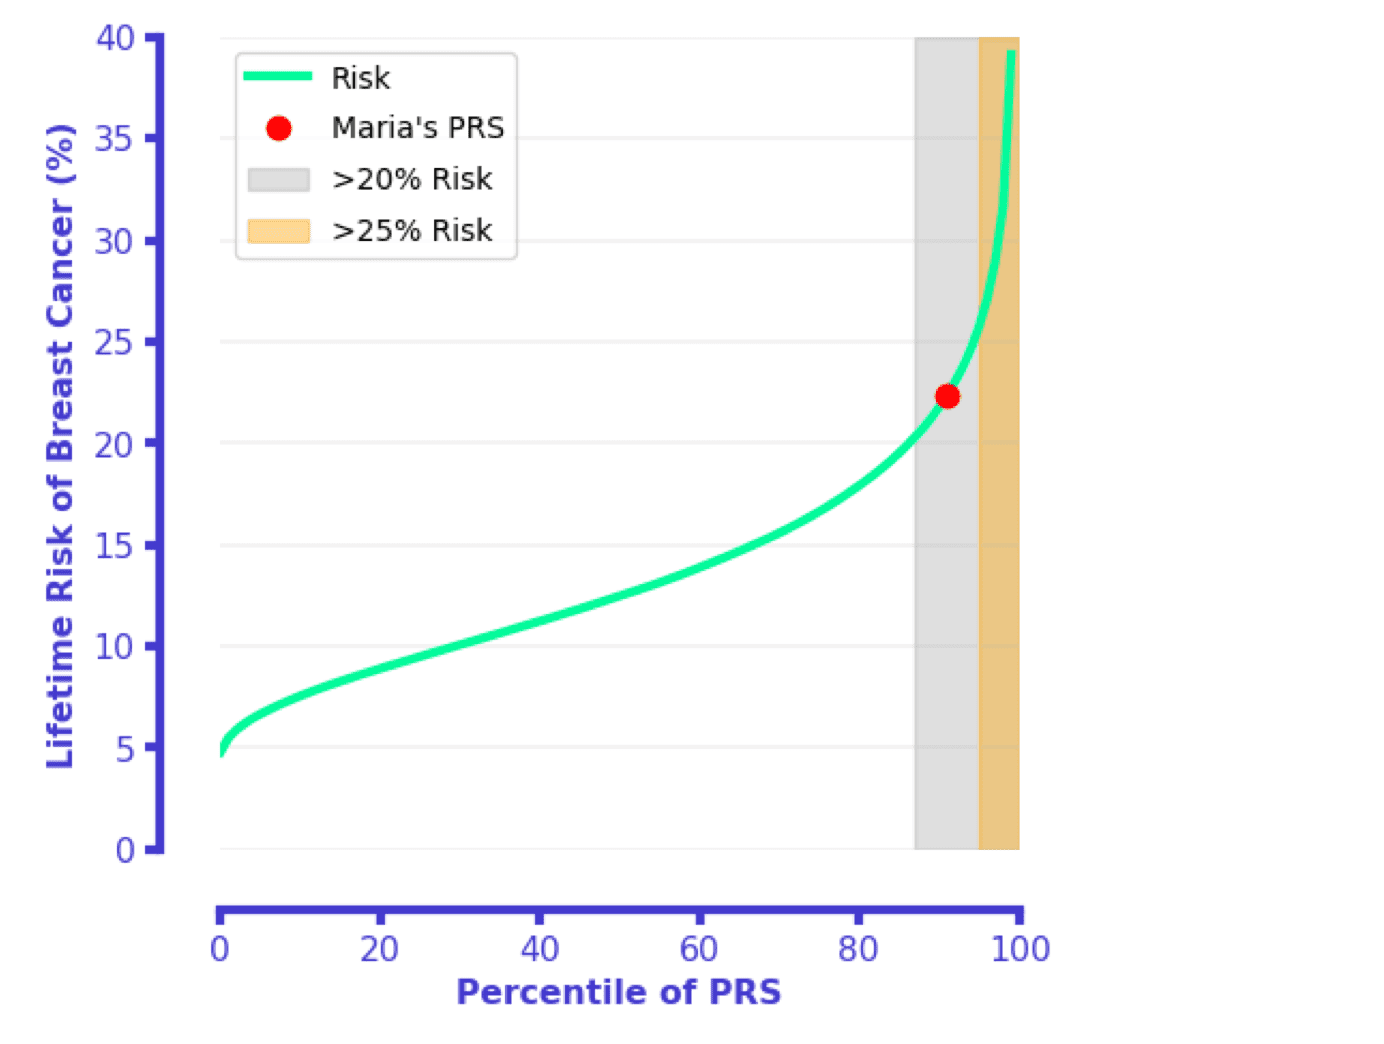

Polygenic Risk Score for Breast Cancer: a Clinical Use Case

This document outlines an approach for using a Polygenic Risk Score (PRS) in a breast cancer clinical pathway.

Polygenic risk scores for breast cancer prevention: a guide for physicians

A how-to guide for how to use breast cancer polygenic risk scores

Allelica, Inc’s risk reports align with disease specific guidelines to communicate an individual’s risk of disease based on their PRS. Risk can be communicated as relative or absolute...